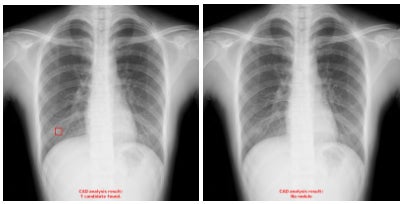

・偽陽性の改善例

肋骨、血管、ニップル等が重なり合い、透過度が減少している領域に対して旧モデルでは偽陽性が発生しておりましたが、新モデルでは改善されています。(4)

※左:旧モデルによる解析結果、右:新モデルによる解析結果